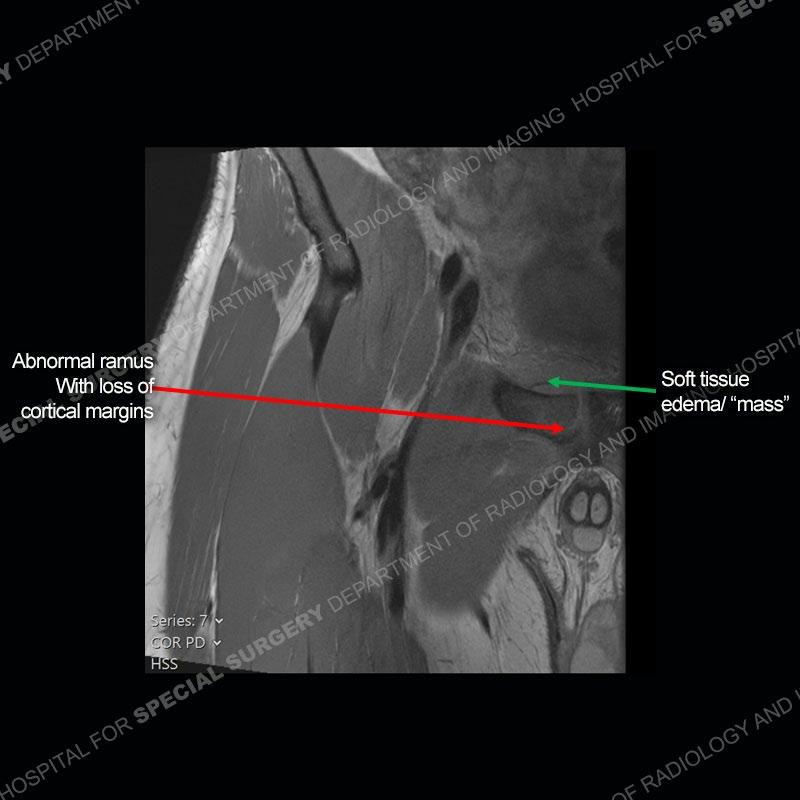

Radiographs did not demonstrate any clear abnormality. The MRI shows markedly abnormal signal of the right superior pubic ramus and abnormal signal/”mass” extending into the adjacent soft tissue. The inferior articular surface of the ramus showed what was thought to be bony destruction. CT examination shows a destructive process of the right superior pubic ramus.

Subsequent MRI in a very short time interval shows markedly increased abnormality of the ramus and increased edema and “mass” of the soft tissue. Post contrast imaging shows multiple, rim enhancing collections of the soft tissue and similar albeit less conspicuous enhancing collection of the ramus.